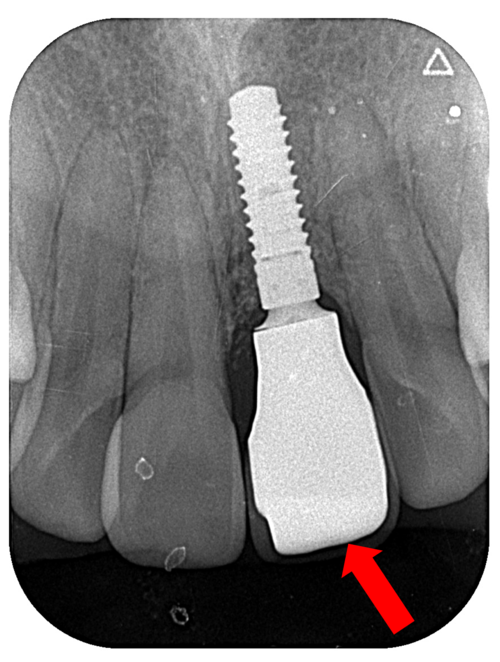

こちらが抜歯前のレントゲン写真です。左上1番目の歯の頭が大きく欠け、歯の根も折れています。

こちらがインプラント手術後のレントゲン写真です。